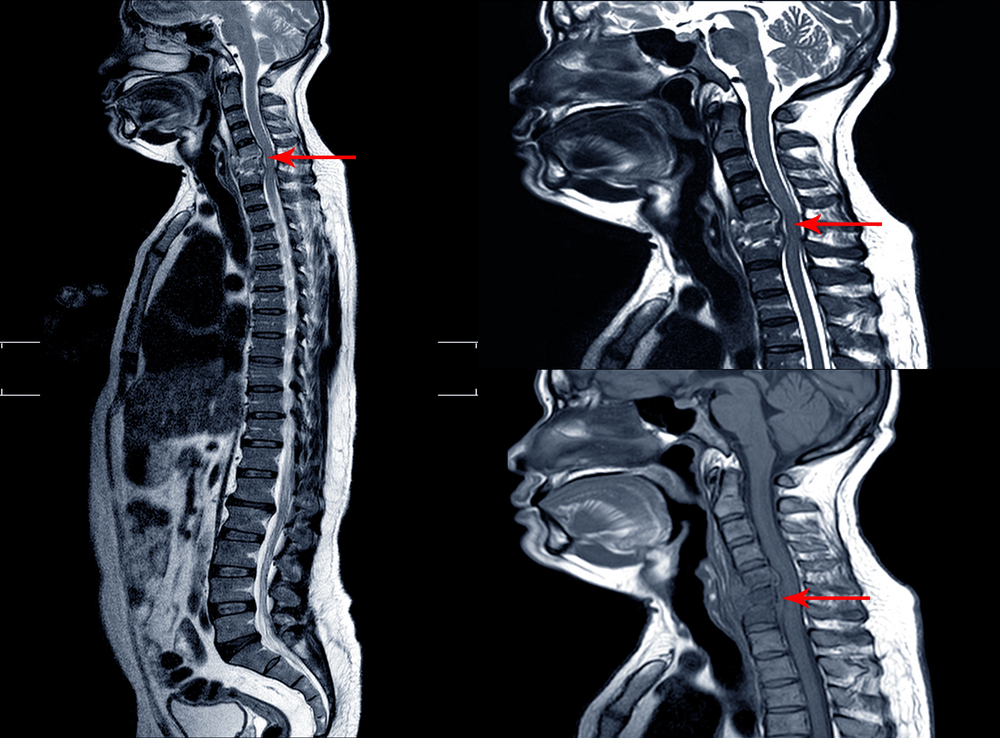

Is neck surgery designed to prevent further degeneration of the cervical spine always necessary?

Marc Darrow, MD. JD. I frequently see patients who have been told by another physician that they require neck surgery. This procedure, they are told, is necessary to avert further deterioration of their cervical spine. Many of these patients are frightened by the information provided by their doctor. Some have been warned that if their […]